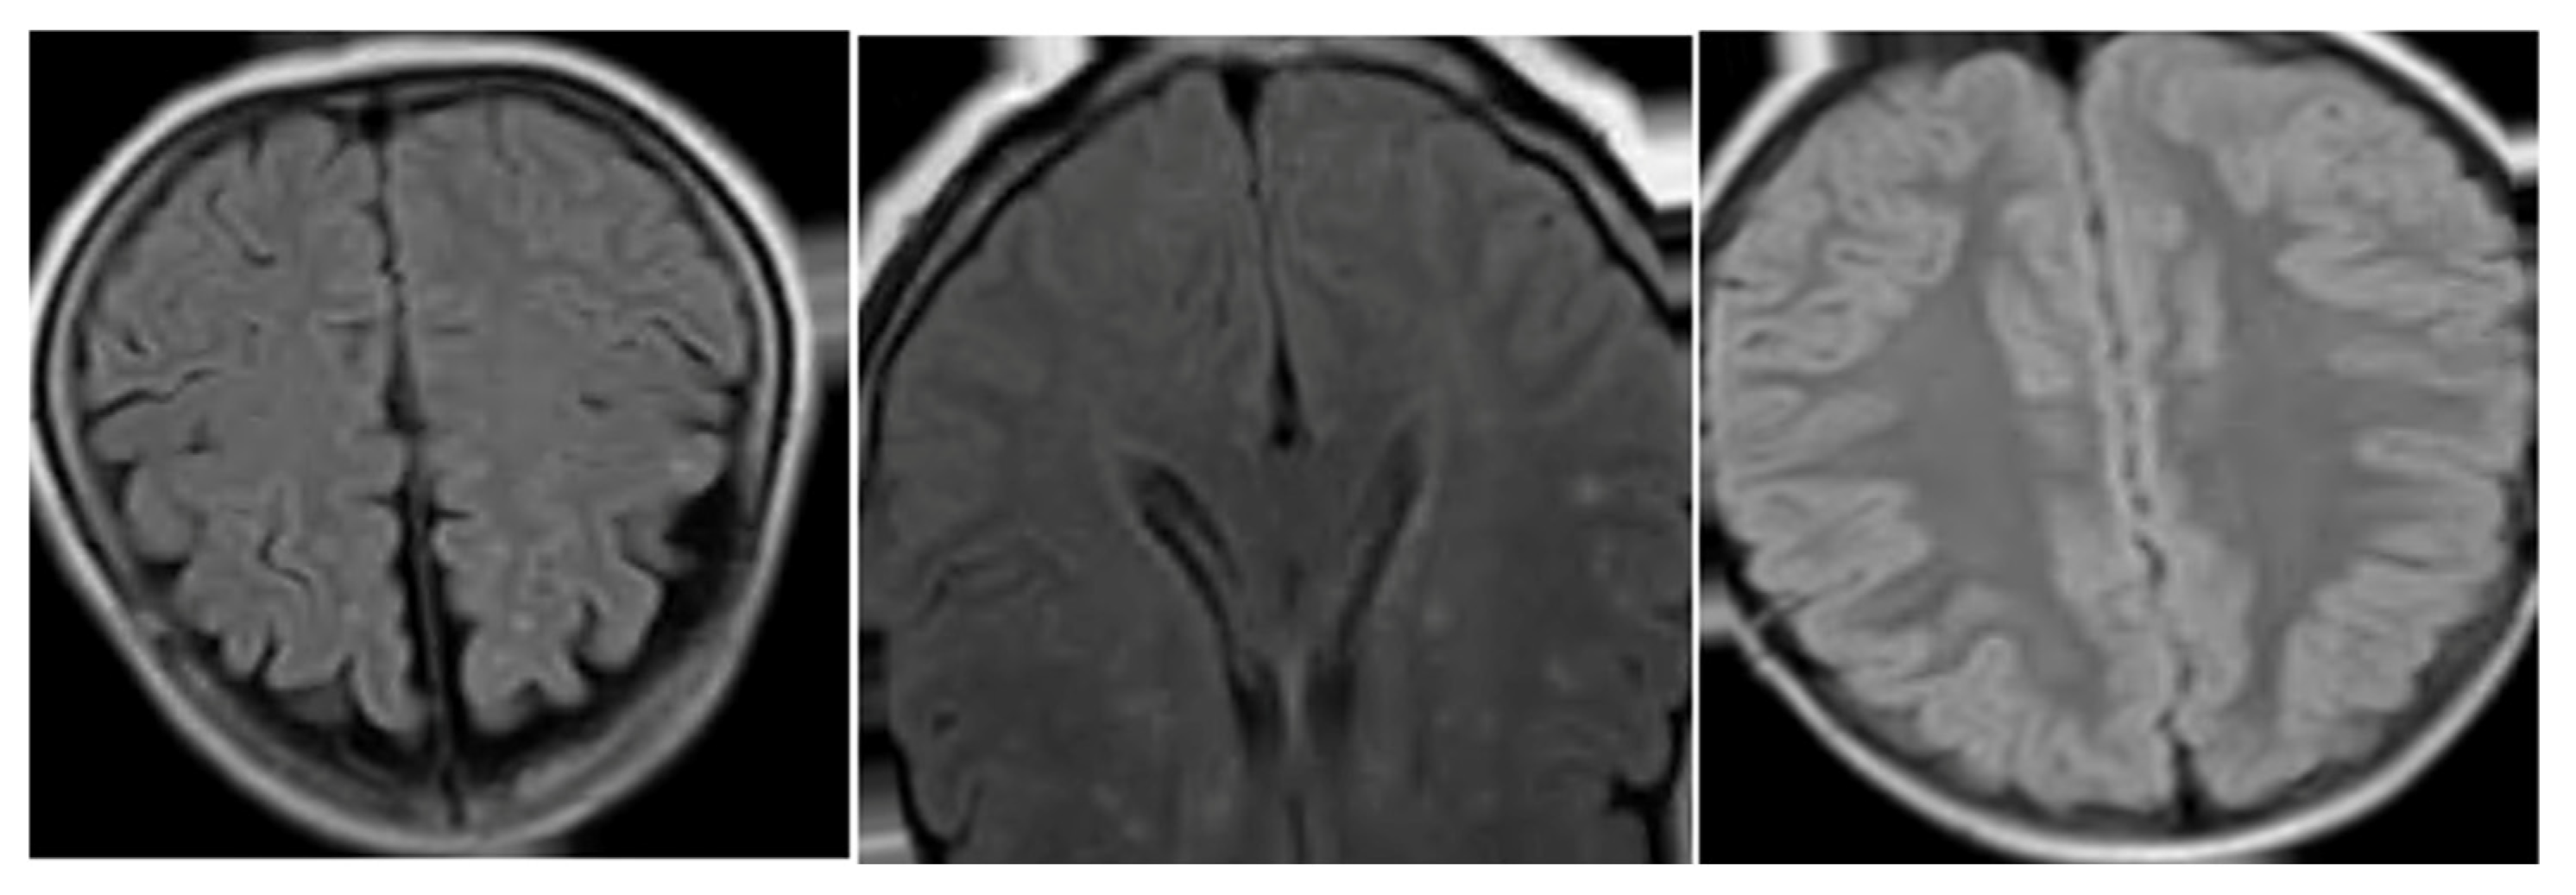

Artifacts and Noise Reduction

Bias Field Correction

Image Normalization

Resampling and Spacing Normalization